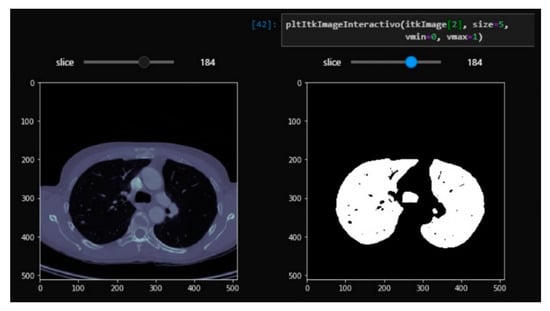

3.1. From dicom to 3D Models with Automatic Segmentation

2. Materials and Methods

2.3. Computer Vision Algorithms

- Processed by thresholding: based on keeping the voxels whose intensities are within a fixed range, and setting the rest to a fixed value that is interpreted as the background of the image. This process is useful for separating structures when no different regions with similar intensities exist.